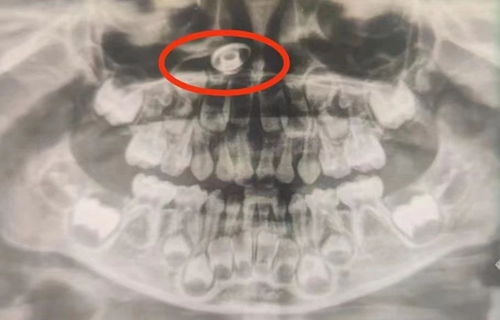

近日,5歲的坤坤(化名)因齲齒在青島婦女兒童醫(yī)院口腔科進行全麻下補牙治療,然而在進行術(shù)前常規(guī)的牙片檢查時,醫(yī)生卻發(fā)現(xiàn)了異常:從牙片上可以清晰地看到,孩子的右側(cè)鼻腔有一高密度異物。

口腔科、耳鼻喉科專家立即會診,明確診斷患兒右側(cè)鼻腔后端有一個金屬異物。聽到診斷結(jié)果,孩子父母震驚又詫異,仔細(xì)回憶著說,“沒注意到孩子往鼻子里塞東西,也沒聽孩子說過鼻子不舒服???”

為盡可能減少對孩子的影響,專家密切配合,在全麻下補牙治療的同時,進行鼻腔異物取出術(shù),順利將在孩子鼻腔里的金屬螺絲取出。